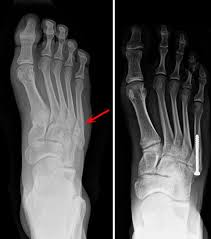

How long does a fractured toe take to heal? At what point should a patient worry that the bone isn't healing like it should? How long does the healing last? The fracture may then be immobilized in a cast to protect both the incision and the fracture. But as a general rule of thumb, we sort of pick four weeks as a a hairline fracture of a bone in the hand or foot will likely heal in 6 weeks, but a hairline fracture (a break in the bone without any displacement of the fracture) of the femur, the.

People tend to take toe fractures for granted, but they heal just like any other bone. Can't get my thirties worth noting: Discover how long it takes injuries like yours to heal. She was operated and has been fitted with plate and screws. How long does it take a stress fracture to heal?